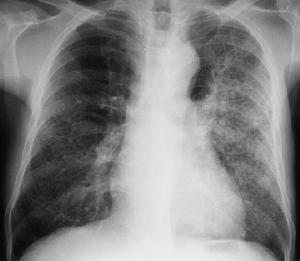

1.檢驗作血白細胞計數及分類。漱口後咳深部痰直接塗片作細菌檢查。應儘量在抗生素套用前作痰、血細菌培養及藥物敏感試驗,培養應反覆多次。作痰培養細菌菌落計數,對於判斷是否是致病菌有一定幫助。疑為軍團菌肺炎者,需作痰或下呼吸道分泌物軍團菌分離,或以直接螢光抗體法,檢測病理標本中的軍團菌,或行血清抗體檢查。2.胸部X線檢查注意陰影特點、部位和範圍。肺炎(鏈)球菌肺炎多呈段或葉大片狀模糊炎性浸潤;金葡菌肺炎系壞死性肺炎,可呈大片絮狀、濃淡不均影,常有一個或多個透亮區,也可為支氣管肺炎表現,血源性者為散在多發膿腫陰影;肺炎克雷伯桿菌肺炎亦呈壞死性表現,上葉多見,呈斑片狀或大葉性,易形成空洞,需與肺結核鑑別,或呈兩側支氣管肺炎改變;軍團菌肺炎早期為單側少量斑片狀實質浸潤,可迅速發展為多肺葉段,下葉多見。